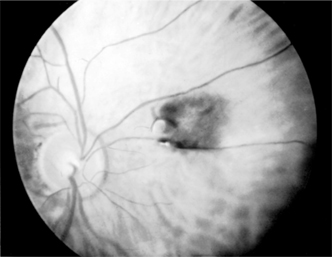

Figure 7-9

Figure 7-9: Malignant melanoma of the choroid, macular area, left eye (drawing). (Courtesy of F Cordes.)

It has been estimated that intraocular malignant melanoma occurs in 0.02-0.06% of the total eye patient population in the USA. It is seen only in the uveal tract and is the most common intraocular malignant tumor in the white population. It is almost always unilateral. Eighty-five percent appear in the choroid (Figure 7-9), 9% in the ciliary body, and 6% in the iris.

This tumor may be seen in its early stages only accidentally during routine ophthalmoscopic examination or because of blurring due to macular invasion. Blood-borne metastases may occur at any time. Glaucoma may be a late manifestation.